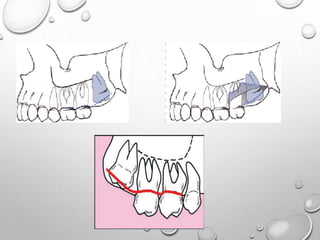

Uprighting mesially impacted lower third molars

with skeletal anchorage

Manuel et al

jco,july 2016

• An orthodontic mini-implant is inserted interproximally on

the buccal side of the alveolar ridge, with the exact

location determined by clinical and radiographic

assessment of the available space.

• With direct anchorage from the mini-implants, there is no

risk of anchorage loss or undesired tooth movement.

Extraction and associated risks such as nerve damage,

TMD, and improper wound healing are avoided.